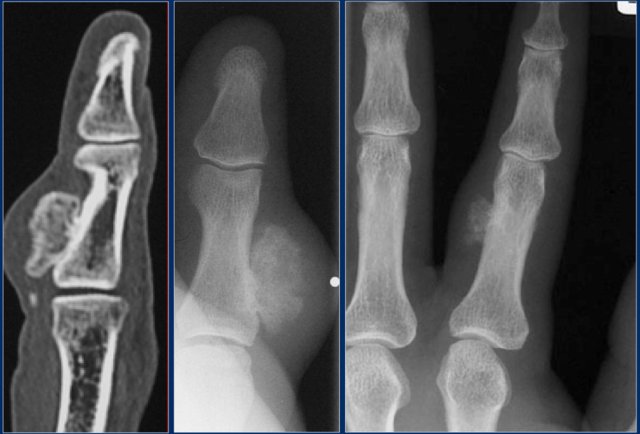

Subungual exostoses

Subungual exostoses are bony projections which arise from the dorsal surface of the distal phalanx, most commonly of the hallux.

These lesions are not osteochondromas, but consist of reactive cartilage metaplasia.

The radiographic appearance and location are typical.

Nora's lesion

Here two patients with a bizar parosteal osteochondromatous proliferation (BPOP), also called Nora's lesion.

This benign reactive process is most commonly found adjacent to the cortex of phalanges of hands or feet (75%).

The cortical bone and bone marrow compartment are not involved.

Rapid growth of the mineralized mass is not uncommon.